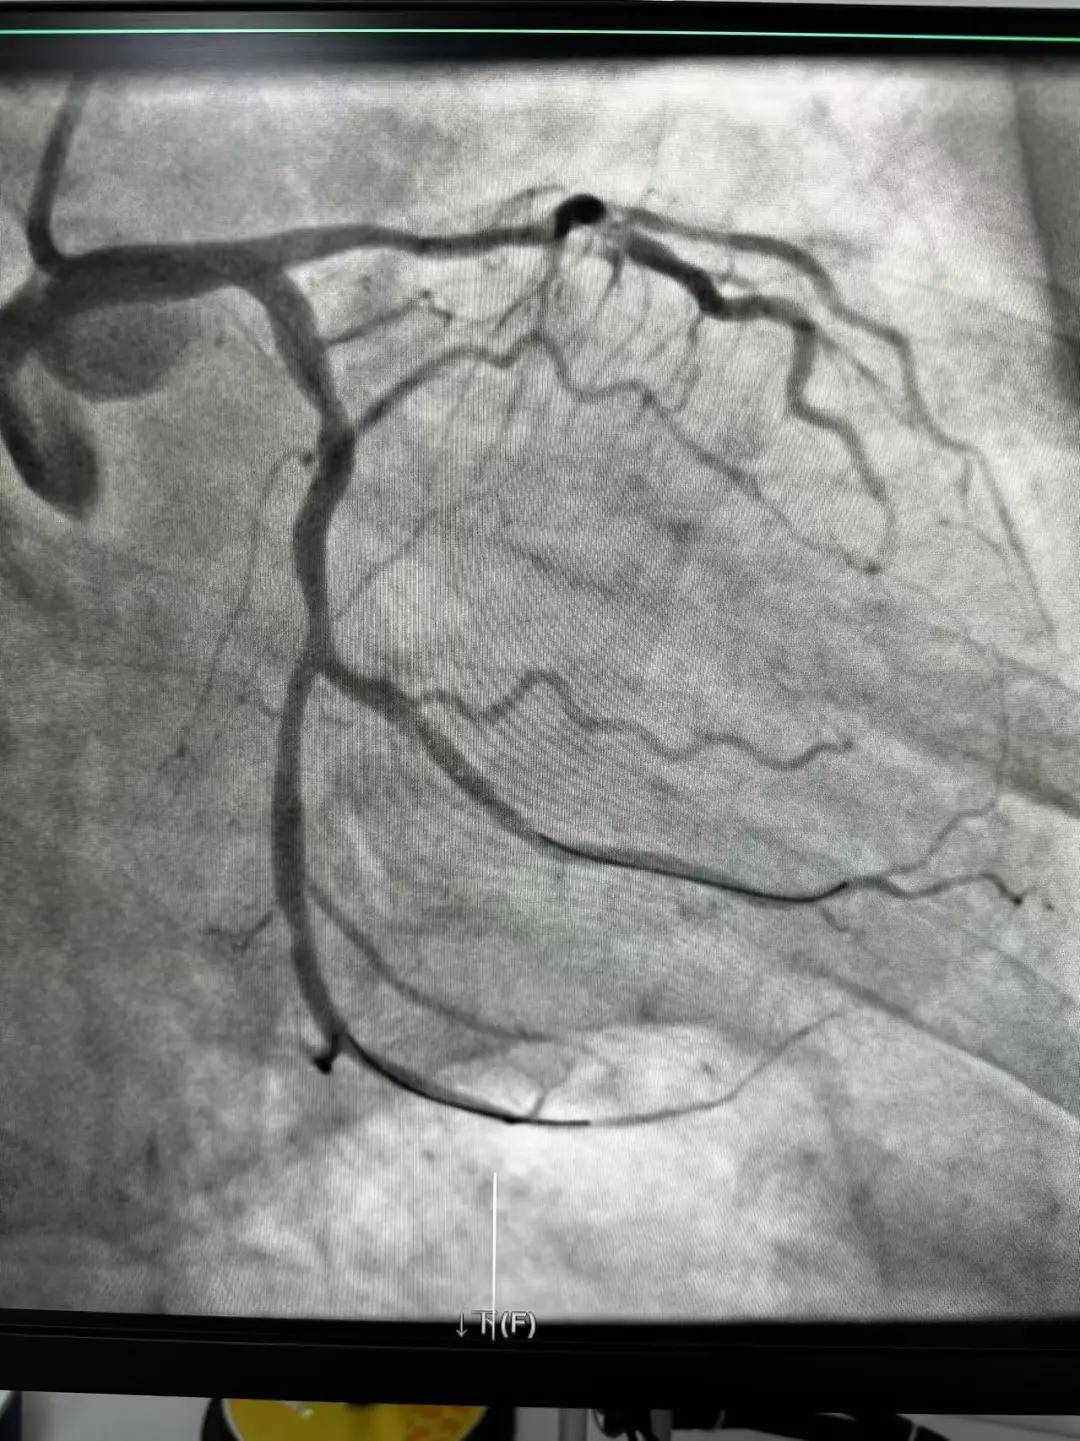

今天最后一臺手術(shù),是一個嚴(yán)重三支病變的病人,患者張大爺,71歲,以“突發(fā)胸悶胸痛3小時(shí)”為主訴入院。經(jīng)心電圖檢查后示室上性心動過速,以“冠心病、心絞痛、心律失常”為診斷收住入心內(nèi)科。心內(nèi)科團(tuán)隊(duì)通過審慎評估,決定給予患者冠狀動脈造影術(shù)及冠狀動脈內(nèi)支架置入術(shù)。

許先生,52歲,大貨司機(jī),在鶴壁至安陽卸貨過程中,突發(fā)胸悶胸痛,伴大汗1.5小時(shí)。 患者繞行安陽,于11點(diǎn)38分到達(dá)我院大門,11點(diǎn)41分首份心電圖,提示患者下壁心肌梗死。 起病急,病程短,情況十分危險(xiǎn),如果血管完全堵塞將直接威脅患者生命,亟需疏通堵塞血管進(jìn)行血運(yùn)重建。

穿刺、造影、放支架……兩個手術(shù)間各個環(huán)節(jié)緊張卻有序地進(jìn)行著!在心內(nèi)科團(tuán)隊(duì)精準(zhǔn)、默契的配合下,兩臺手術(shù)順利完成! 兩名患者的快速、同時(shí)、成功救治,得益于殷都區(qū)人民醫(yī)院醫(yī)務(wù)人員快速的應(yīng)急能力、過硬的急救技能,同時(shí)更得益于導(dǎo)管室同開臺,保障了救治的迅速有效。